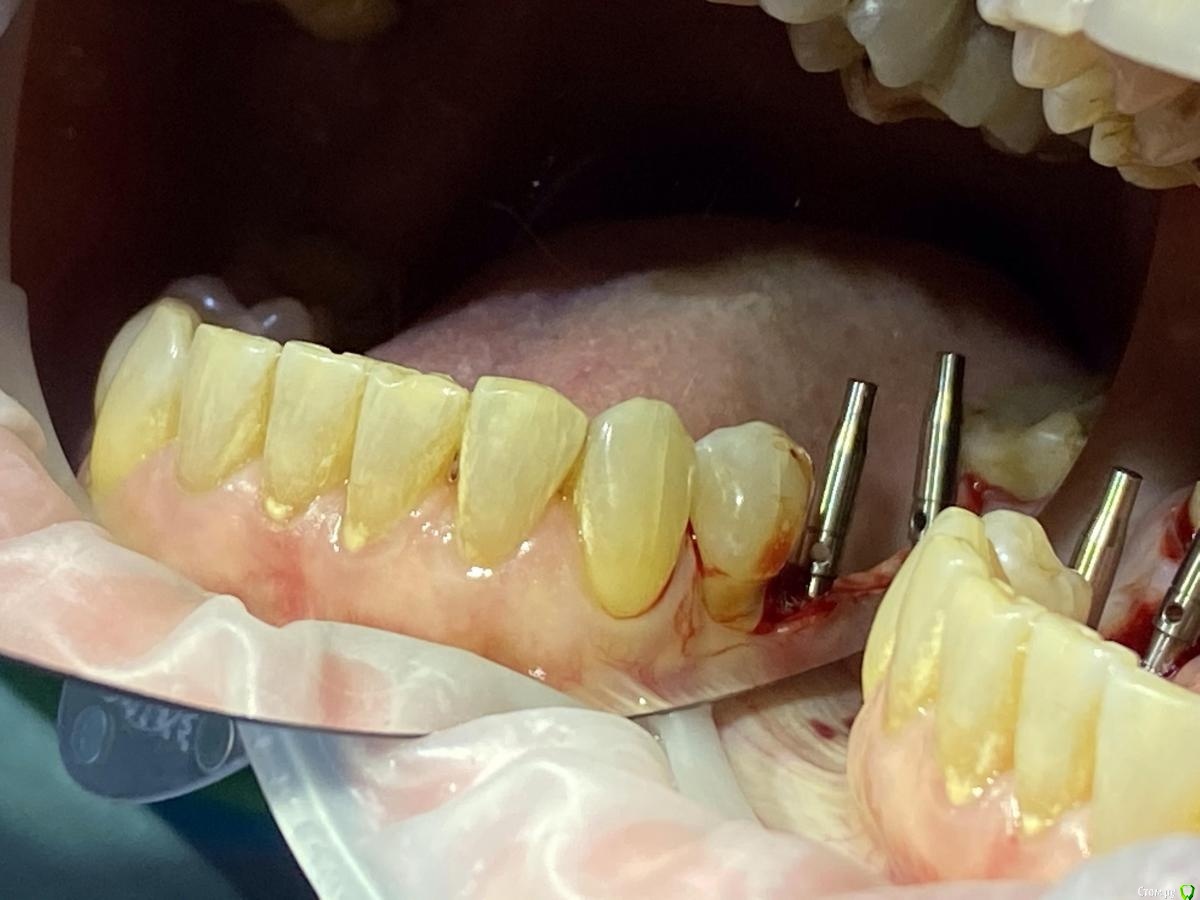

Женька Опубликовано 28 ноября, 2020 Поделиться Опубликовано 28 ноября, 2020 (изменено) Приветствую коллеги. В общем три недели назад 07.11.20 установил пациентке 2 имплантата в позиции 45-46. Гребень по ширине был около 6.5мм в области 4.5 и около 7.2мм в области 4.6 (с учётом заглубления на 1.5-2мм). Это была наверное первая имплантация во время которой я чувствовал себя спокойно и расслабленно. Всё прошло хорошо, немного покопался с непосредственным введением имплантатов, тк никак не хотели топиться на нужные 1.5мм. Поэтому пробовал методику с выкручиванием на пару витков и снова закручиванием. Особого толку не получил, потому взял финальную фрезу и чуть углублял ложе. Так несколько раз, тк боялся всё-таки немного что задену менталис и нлн. Ввиду того, что биотип у пациентки тончайший и язычно было совсем-совсем тонко - заглушки и швы. Назначил нпвс, ванны хг, аб терапию. Но на утро следующего дня пациентка сказала, что чувствует себя шикарно, решили что нпвс оставим, а аб терапию применять не будем (и грешу что в этом мою ошибка).Через неделю сняли швы, всё отлично.Спустя два дня после снятия начались какие-то "костные" боли, как говорит пациентка в области 4.5 импланта. Которые то отпускают, то снова наплывают. На 4.4 есть дефект твердых тканей (на фото виден), но судя по всему беспокоит не он .Пальпация вестибулярно в проекции 4.5 импланта болезненна, небольшая гиперемия, отёка нет. Гигиену пациентка запустила, тк боялась туда залезать и чистить. Снимки прилагаю первые два от 07.11, два последующих 28.11. Ну и внутри ротовые день операции и сегодняшние числа.Похоже 4.5 на выход? своими "туда-сюда" наверняка я нагрел всё что можно... снова расстройство в той работе, где накосячить предельно сложно... Добавка: пить аб ведь сейчас уже бесполезно? Изменено 28 ноября, 2020 пользователем Женька Ссылка на комментарий

колесников Опубликовано 28 ноября, 2020 Поделиться Опубликовано 28 ноября, 2020 (изменено) Имплант 13 мм? Зачем? При планировании видно, что он упирается апексом в кортикалку. По этому и поставить не могли сразу. Торк 45. Если имплант плотно контактирует с компактной пластинкой,она резорбируется окончато,со всеми вытекающими. Стоило выбрать имплант 8.5мм. Если притопили имплант,зачем поставили заглушку? Имплант зарастёт придётся выпиливать ,откапывать заглушку,ломать то что наросло непосильным трудом. Хороший торк-ставьте рабочий фдм. Сомнения-мелкий фдм или заглушка +1. Рекомендую сделать контрольный кт и поставить фдм Изменено 28 ноября, 2020 пользователем колесников 5 Ссылка на комментарий

Женька Опубликовано 29 ноября, 2020 Автор Поделиться Опубликовано 29 ноября, 2020 Я бы сейчас сделала три вещи :дала курс антибиотика шикарной женщине,гигиену навела бы во рту или хотя бы в этой области,депульпировала премоляр.Чтобы прикрыться со всех сторон. Выждать. Вынуть всегда успеется.А потом.. может,там уже формики просятся?Три недели, не рановато ли? По поводу премоляра, терапевта напрягу. А на каком режиме Вы закручиваете/выкручиваете?20оборотов на торке 30, далее руками динамометрическим ключом. Имплант 13 мм? Зачем? При планировании видно, что он упирается апексом в кортикалку. По этому и поставить не могли сразу. Торк 45. Если имплант плотно контактирует с компактной пластинкой,она резорбируется окончато,со всеми вытекающими. Стоило выбрать имплант 8.5мм.Импланты 10мм каждый, разметка на планировании - глубина препарирования с учётом заглубления. Проблема то как раз в области 4.5 импланта, там нет такого контакта с кортикой апикально, а область шейки хорошо развальцевал кортикальной фрезой. 4.6 где как раз контакт кортикальный спокоен. Если притопили имплант,зачем поставили заглушку? чтобы избежать проблем как в предыдущем моём случае, где тоже было тонко язычно. Потому хотел на этапе раскрытия работать с десной и язычно перемещать объём. http://forum.stom.ru/topic/40254-otsrochennaia-implantatciia/ Сомнения-мелкий фдм или заглушка +1. что значит заглушка +1? Если сейчас залезть и выкрутить заглушки не велики ли риски прокручивания имплантата...ведь на 3-5 недели самая большая потеря первичной стабильности происходит. Ссылка на комментарий